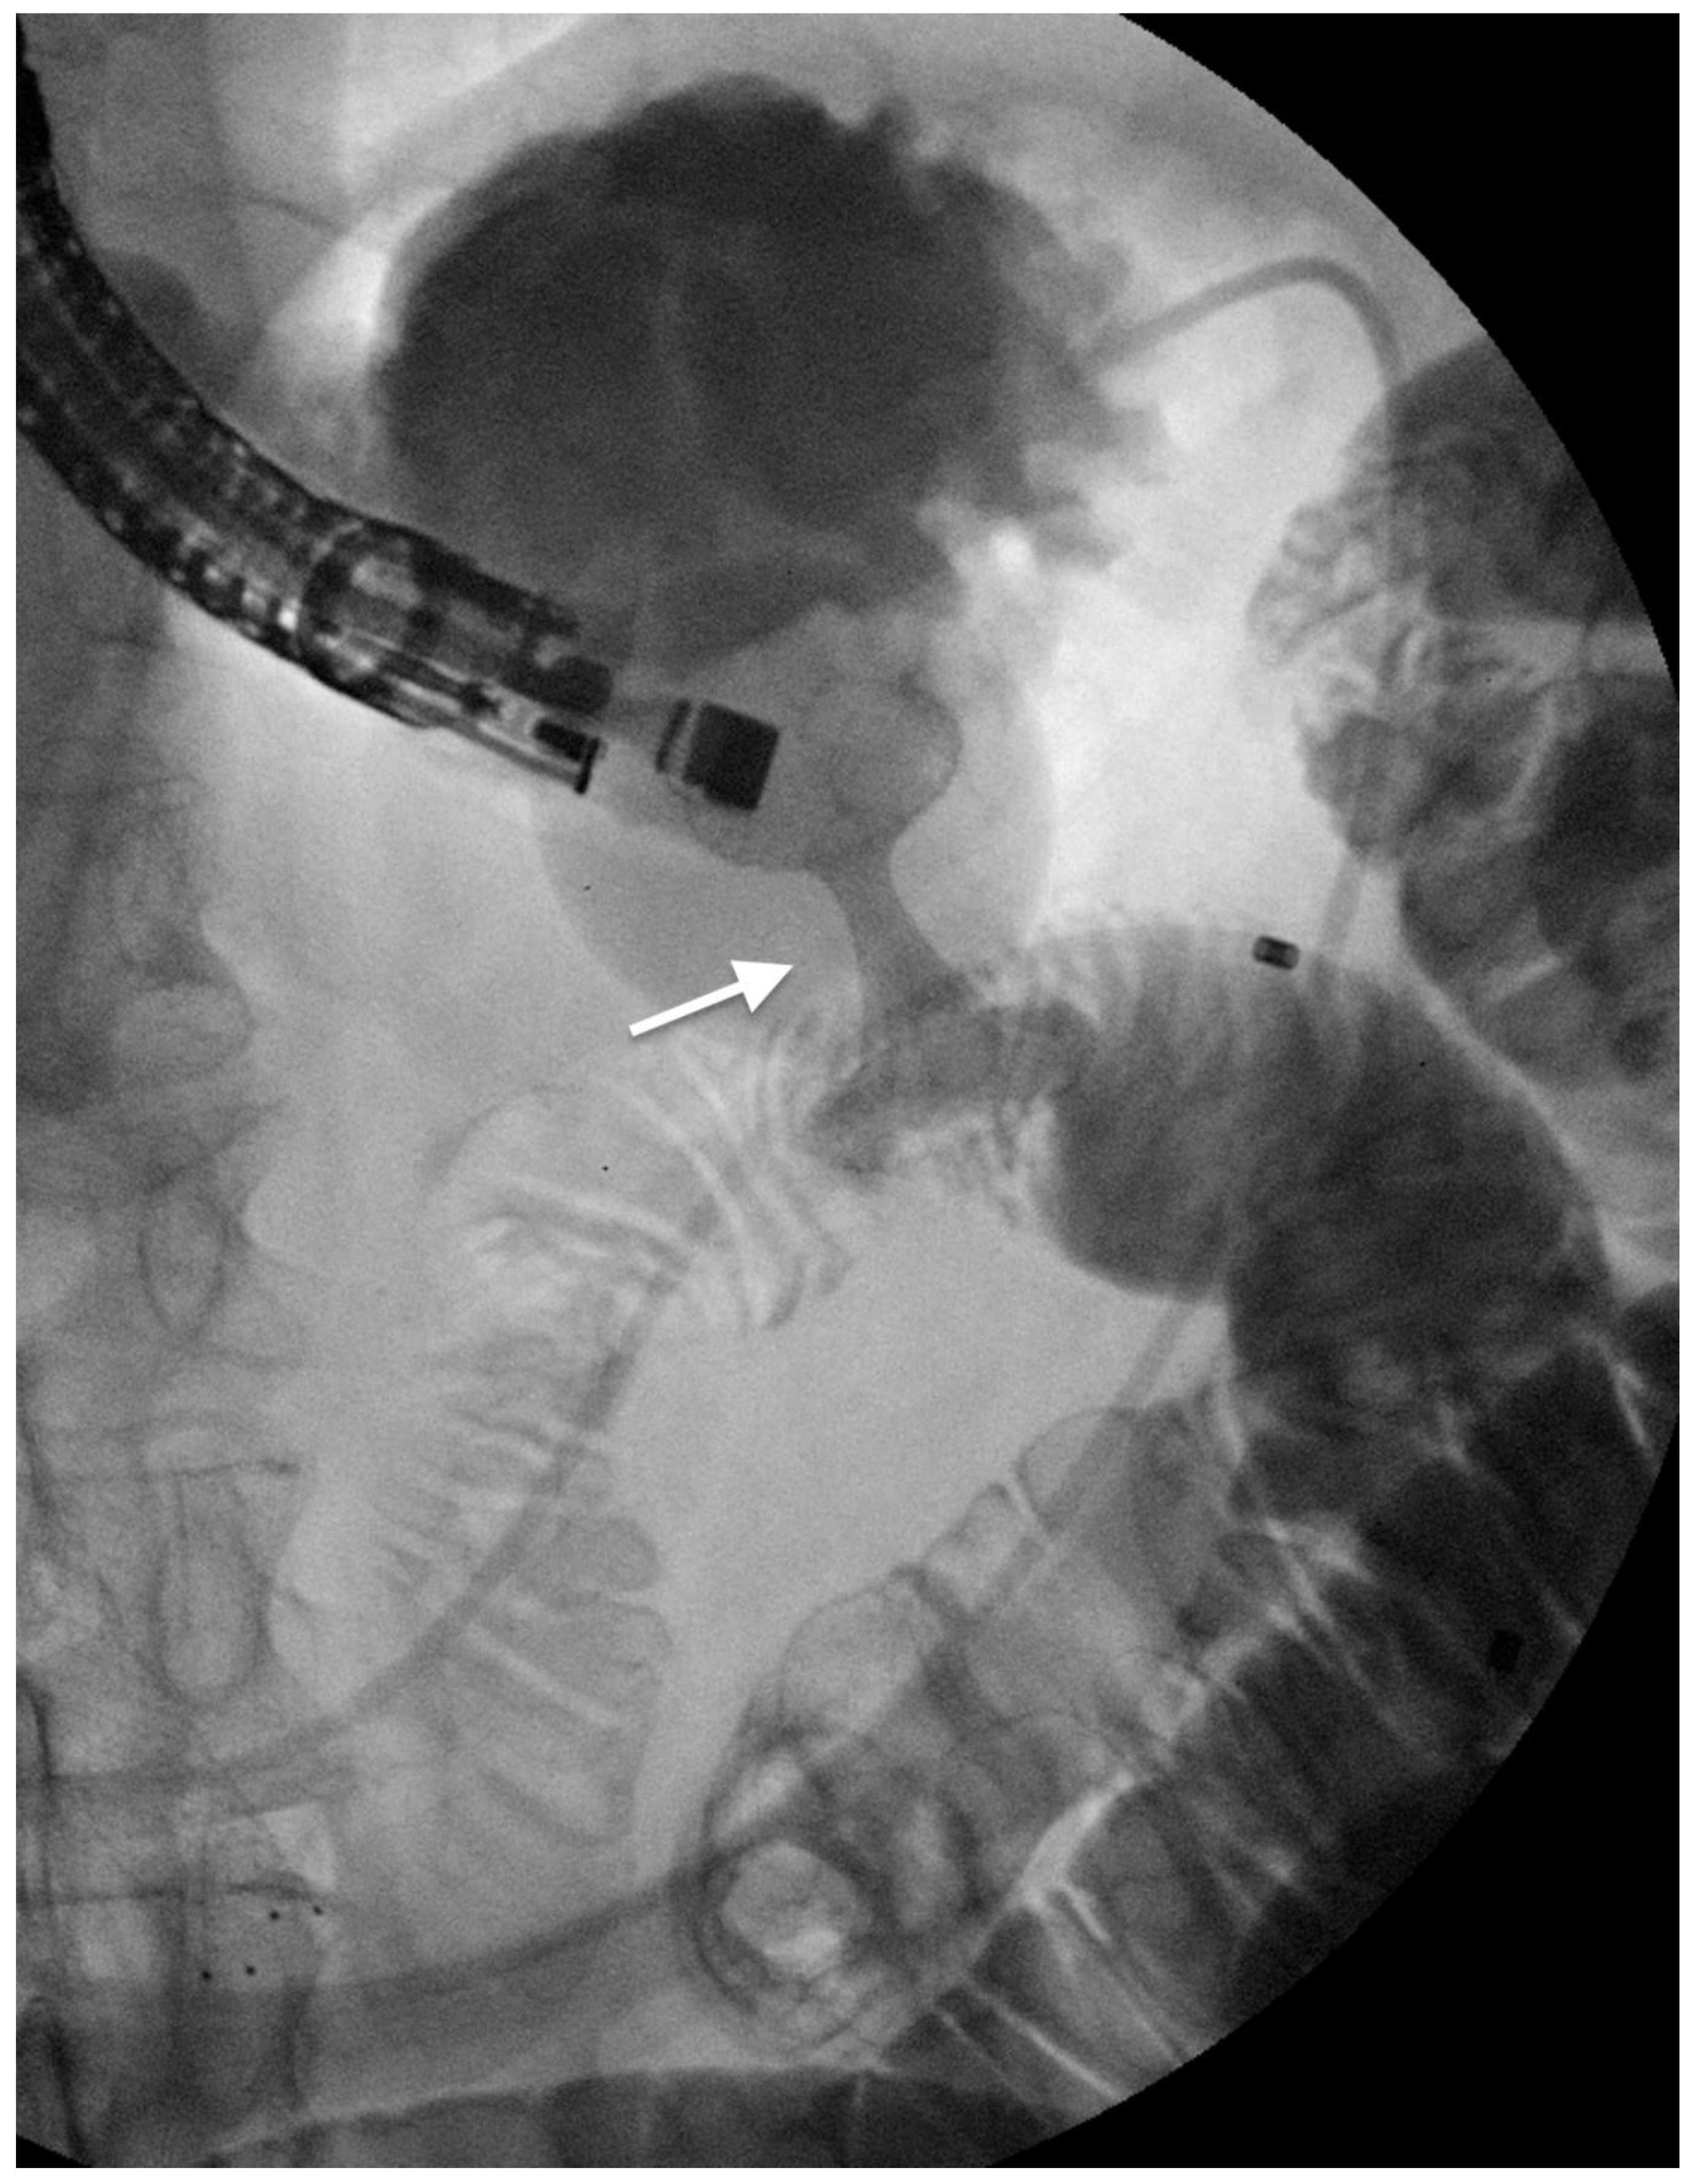

2.1. ERCP-Guided Biliary Drainage

3.1. Endoscopic Self-Expandable Metal Stent

3.2. EUS-Guided Gastro-Enteral Anastomosis